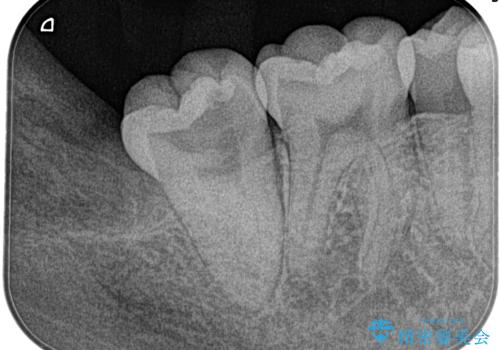

湾曲根管。精密根管治療

担当医 河口智英